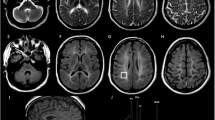

We investigated the proteolipid protein (PLP) gene in two brothers in a Japanese family with a connatal form of Pelizaeus-Merzbacher disease (PMD). Direct sequencing of the PLP gene revealed an A-to-T transition in exon 4, which led to an Asp-to-Val substitution at re-sidue 202. Their mother was confirmed to be heterozygous for the mutation. The mutation was not found in 78 X-chromosomes of normal Japanese individuals. A correlation between the clinical severity of the disease in the brothers and the Asp202-to-Val mutation in the PLP gene was suggested.